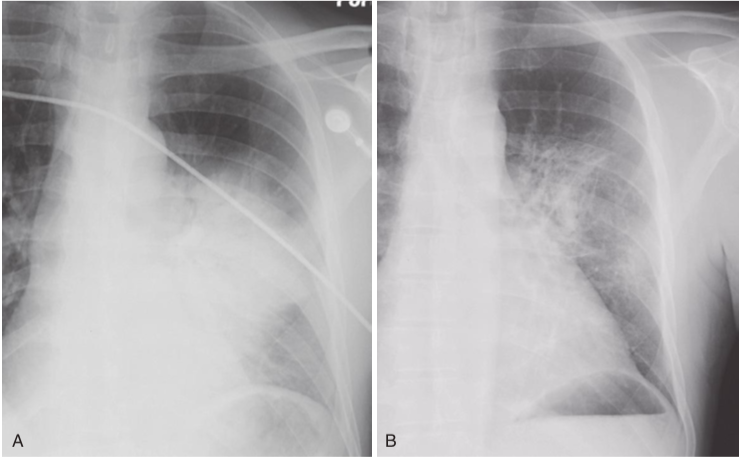

Large left pleural effusion.

The left hemithorax is completely opacified, and there is a shift of the mobile mediastinal structures, such as the trachea (solid black arrow) and the heart(dotted black arrow), away from the side of opacification. This is characteristic of a large pleural effusion, which can act like a mass. In most adults, it requires about 2 L of fluid to fill or almost fill the entire hemithorax such as shown here.